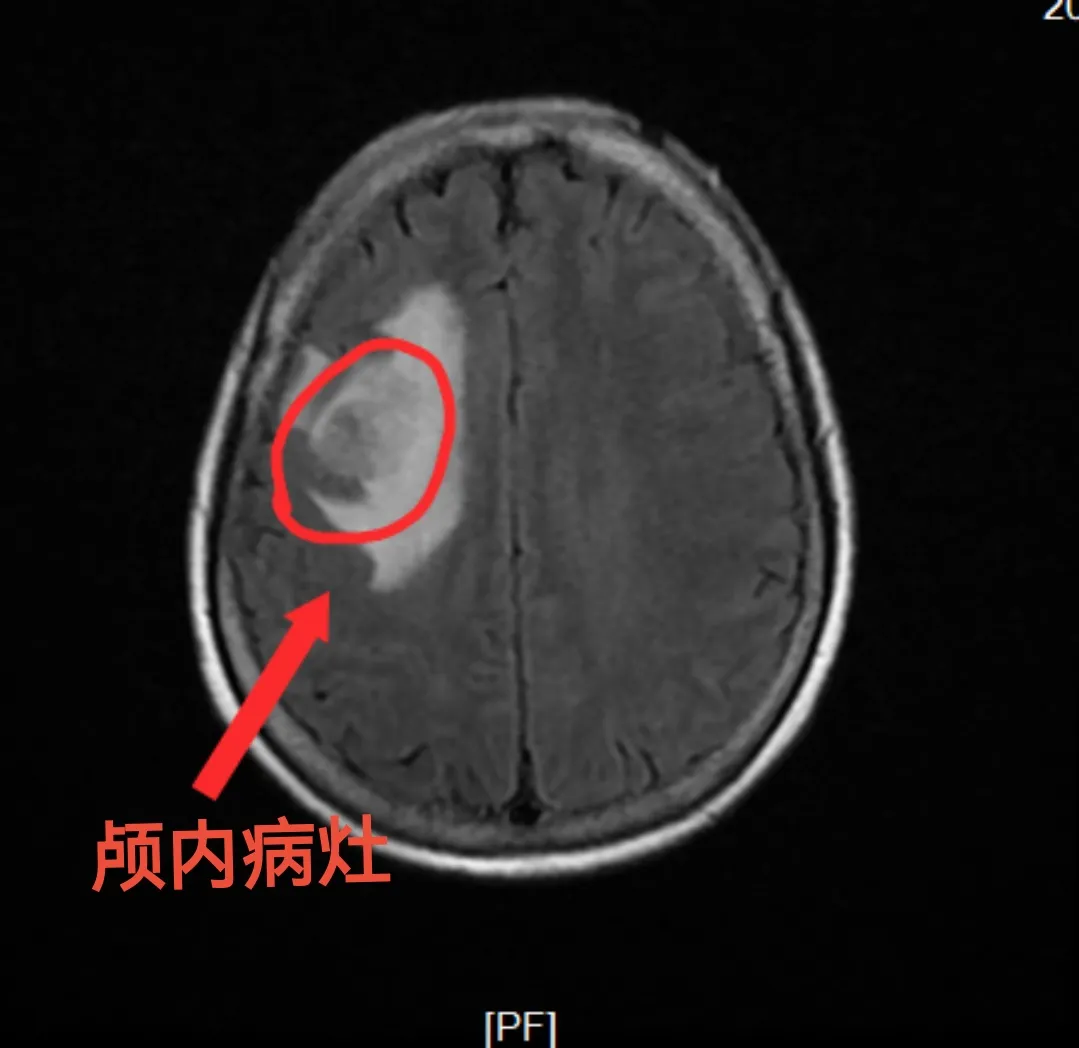

秦女士因持续性头痛来院就诊,经检查其颅内存在不明性质的病灶。面对这个潜在的“隐形炸弹”,明确其病理性质是决定下一步治疗的关键。传统的开颅活检创伤大、恢复慢,往往让患者在治疗前便心生顾虑,甚至望而却步。然而,现代医疗技术为破解这一困境提供了全新方案,我院神经外科蔡璞主任团队经过充分评估,决定为秦女士实施神经外科机器人辅助立体定向脑组织活检术。

手术过程中,机器人系统宛如一位身怀绝技的 “精准助手”——凭借 “超稳定” 的操作精度与 “透视般” 的定位能力,依托术前三维重建的高清影像数据制定最优路径,仅在头皮上切开3毫米的微小切口,便将活检器械精准送达颅内深部病灶,顺利获取了足量且合格的病变组织。整个手术过程仅耗时约十分钟,术中几乎无出血,最大限度降低了手术创伤。

活检组织第一时间被送至病理科加急检测,病理报告清晰明确病变性质为肺癌脑转移。这一关键诊断结果的快速获取,不仅为秦女士后续精准制定靶向治疗、放化疗等综合方案扫清了核心障碍,更让诊疗得以 “少走弯路”,为病情控制争取了宝贵时间。